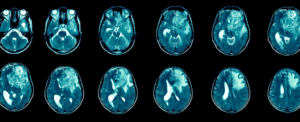

Нове гідрогелеве лікування демонструє успіх в усуненні раку мозку у мишей

Під час випробувань на мишах з агресивними пухлинами мозку гідрогель виявився високоефективним: 50% мишей прожили понад 100 днів без жодних ознак росту пухлини. Це значне покращення порівняно з існуючими методами лікування, які зазвичай продовжують виживання лише на кілька тижнів.